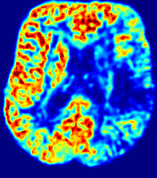

Figure 3: PIANO feature maps for one stroke patient, where the lesion is located in the left hemisphere. Top row: segmented stroke lesion region (white) on different slices, obtained from ISLES 2017. The corresponding slices for the PIANO feature maps are shown in the following rows.

For a better insight into an estimated velocity field 𝐕𝐕{\bf{V}} and diffusion field 𝐃𝐃{\bf{D}}, we compute the following maps: (1) 𝐕rgbsubscript𝐕𝑟𝑔𝑏{\bf{V}}_{rgb}: Color-coded orientation map of 𝐕=(Vx,Vy,Vz)T𝐕superscriptsuperscript𝑉𝑥superscript𝑉𝑦superscript𝑉𝑧𝑇{\bf{V}}=(V^{x},V^{y},V^{z})^{T}, obtained by normalizing 𝐕𝐕{\bf{V}} to unit length and mapping its 3 components to red, green, blue respectively; (2) 𝐕2subscriptnorm𝐕2\|{\bf{V}}\|_{2}: 222 norm of 𝐕𝐕{\bf{V}}; (3) D𝐷D: scalar field in Eq. 5.

Fig. 3 and Fig. 4 show the PIANO feature maps estimated from two ISLES 2017 patients: all are highly consistent with the lesion in both cases. Details of the blood flow trajectories are revealed in 𝐕rgbsubscript𝐕𝑟𝑔𝑏{\bf{V}}_{rgb} by the ridged patterns and the sharp changes of colors in the unaffected (right) hemisphere, while the flat patterns appearing within the lesion provide little directional information about the velocity and indicate low velocity magnitudes. Velocity magnitudes are more directly visualized via 𝐕2subscriptnorm𝐕2\|{\bf{V}}\|_{2}, from which one can easily locate the lesion where 𝐕2subscriptnorm𝐕2\|{\bf{V}}\|_{2} is low. D𝐷D also indicates lower diffusion values in the lesion, though with less contrast potentially due to the fact that it captures the accumulated effect of CA diffusion at the voxel-level.